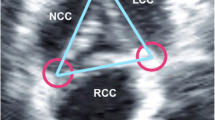

We analyzed the images with Philips QLab software (Philips Ultrasound, Andover, MD, USA). Using MPR, we adjusted the orthogonal imaging planes for optimal visualization of all three aortic coaptation lines (Fig. 1). By moving the red and green planes (Fig. 2), we identified the points where the cusps came together. For each one, we measured the medial and lateral coaptation heights (labelled A and B in Fig. 1) and the coaptation length (labelled C in Fig. 1). We also measured the diameter of the aortic annulus at the level of the ventricular aortic junction (VAJ) in a mid-esophageal long-axis view. All measurements were performed at the end of diastole, which we defined as the 3D frame immediately following closure of the mitral valve.

Images of a normal aortic valve from multiple plane reconstruction (MPR) of the aortic valve. Step 1: The red plane intersects the medial coaptation surface of the non-coronary cusp (NCC) and right coronary cusp (RCC). The yellow line labelled A represents the medial coaptation height. Step 2: The red plane intersects the lateral coaptation surface of the NCC and RCC. The yellow line labelled B represents the lateral coaptation height. Step 3: The two red planes represent the medial and lateral coaptation surfaces, respectively. The yellow line labelled C represents the distance between the two red lines, i.e., the coaptation length

We calculated three CoapSAs for each patient: right coronary cusp/left coronary cusp, right coronary cusp/non-coronary cusp, and left coronary cusp/non-coronary cusp (Fig. 2). Since computer and silicone models have previously shown that the coaptation areas between AV cusps are trapezoidal, we calculated the CoapSA by using the following formula: trapezoid area = coaptation length × (medial coaptation height + lateral coaptation height)/2.7,8 The total CoapSA was calculated by adding all three areas for each valve. To adjust for varying valve sizes, we indexed this value to the diameter of the VAJ.

The concept of CoapSA dates back roughly forty years during the initial development of AV prostheses by Swanson and Clark.8 Using silicon models, they recognized that the CoapSA was not shaped like a simple rectangle, but because of the coronet shape of the valve, it was shaped more like a trapezoid (Fig. 1) with two coaptation heights (a shorter medial one located near the centre of the valve and a longer lateral one located near the outer circumference of the valve) and a distance/length between the two heights. Fig. 1 illustrates this concept using a computer model. The CoapSA cannot be measured by 2D-TEE because of the anatomical relationship between the esophagus and the heart; consequently, only two of three AV coaptation planes can be seen with 2D-TEE.4 Three-dimensional-TEE collects a wide pyramidal volume of information that can then be cropped in an infinite number of ways. Three-dimensional-TEE removes this anatomical barrier and allows the ability to visualize all three coaptation planes.